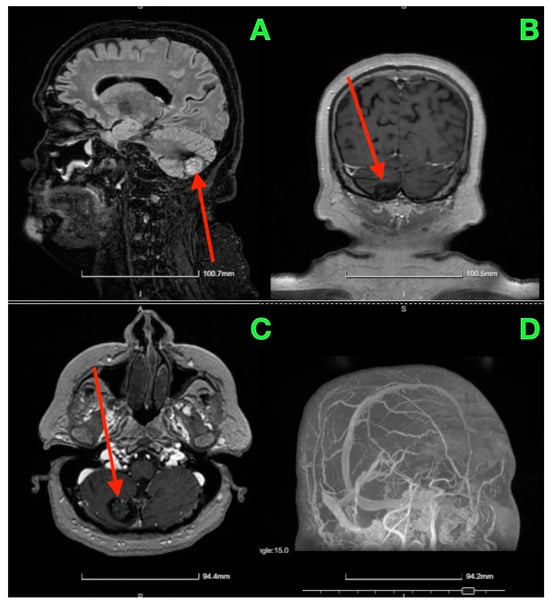

On postoperative day 5, a follow-up CT scan (Figure 3) was performed to assess the surgical site and confirm the absence of postoperative complications such as hemorrhage or hydrocephalus.

Figure 3. Five days post-op CT scan. (A) Demonstrated normal postoperative changes in the right paramedian posterior fossa. The site of the craniectomy was clearly visible, and no signs of residual cavernous malformation were observed. There was no evidence of acute hemorrhage, mass effect, or significant edema in the surrounding cerebellar tissue. Additionally, the ventricular system appeared normal, with no signs of hydrocephalus or midline shift. (B) provided further confirmation of the integrity of the bony structures and the absence of any complications related to the craniectomy. The surgical site remained stable, and there was no abnormal fluid collection or air entrapment within the resection cavity.

The two-month postoperative CT scan (Figure 4) confirmed excellent surgical outcomes. The right cerebellar hemisphere, where the cavernoma had been resected, demonstrated normal postoperative changes, with no signs of residual cavernous malformation or new lesions. The surgical cavity appeared stable, and no signs of hemorrhage or fluid collection were noted.

Figure 4. Two-month follow-up post-op CT scan. (A): Axial CT image of the right cerebellar hemisphere shows normal postoperative changes (red arrows) in the area of the cavernoma resection, with no residual cavernous malformation, new lesions, or signs of fluid collection or hemorrhage. (B): Coronal CT image further confirms the stability of the surgical cavity (red arrow), with no evidence of hemorrhage, recurrent lesions, or abnormal findings in the surrounding structures.